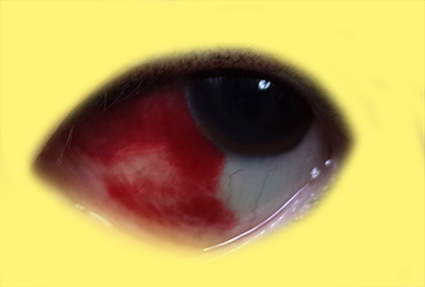

今回どんな感じだったか、一応写真も載せておきますね。

閲覧注意。

まあまあ出血しました。

重力で下にたまってる…( ̄ロ ̄lll)

周りの人に、さすがに怖いわ、って言われました。( ノД`)

もう一回言いますけど、キレイに吸収されましたよ。(>_<)